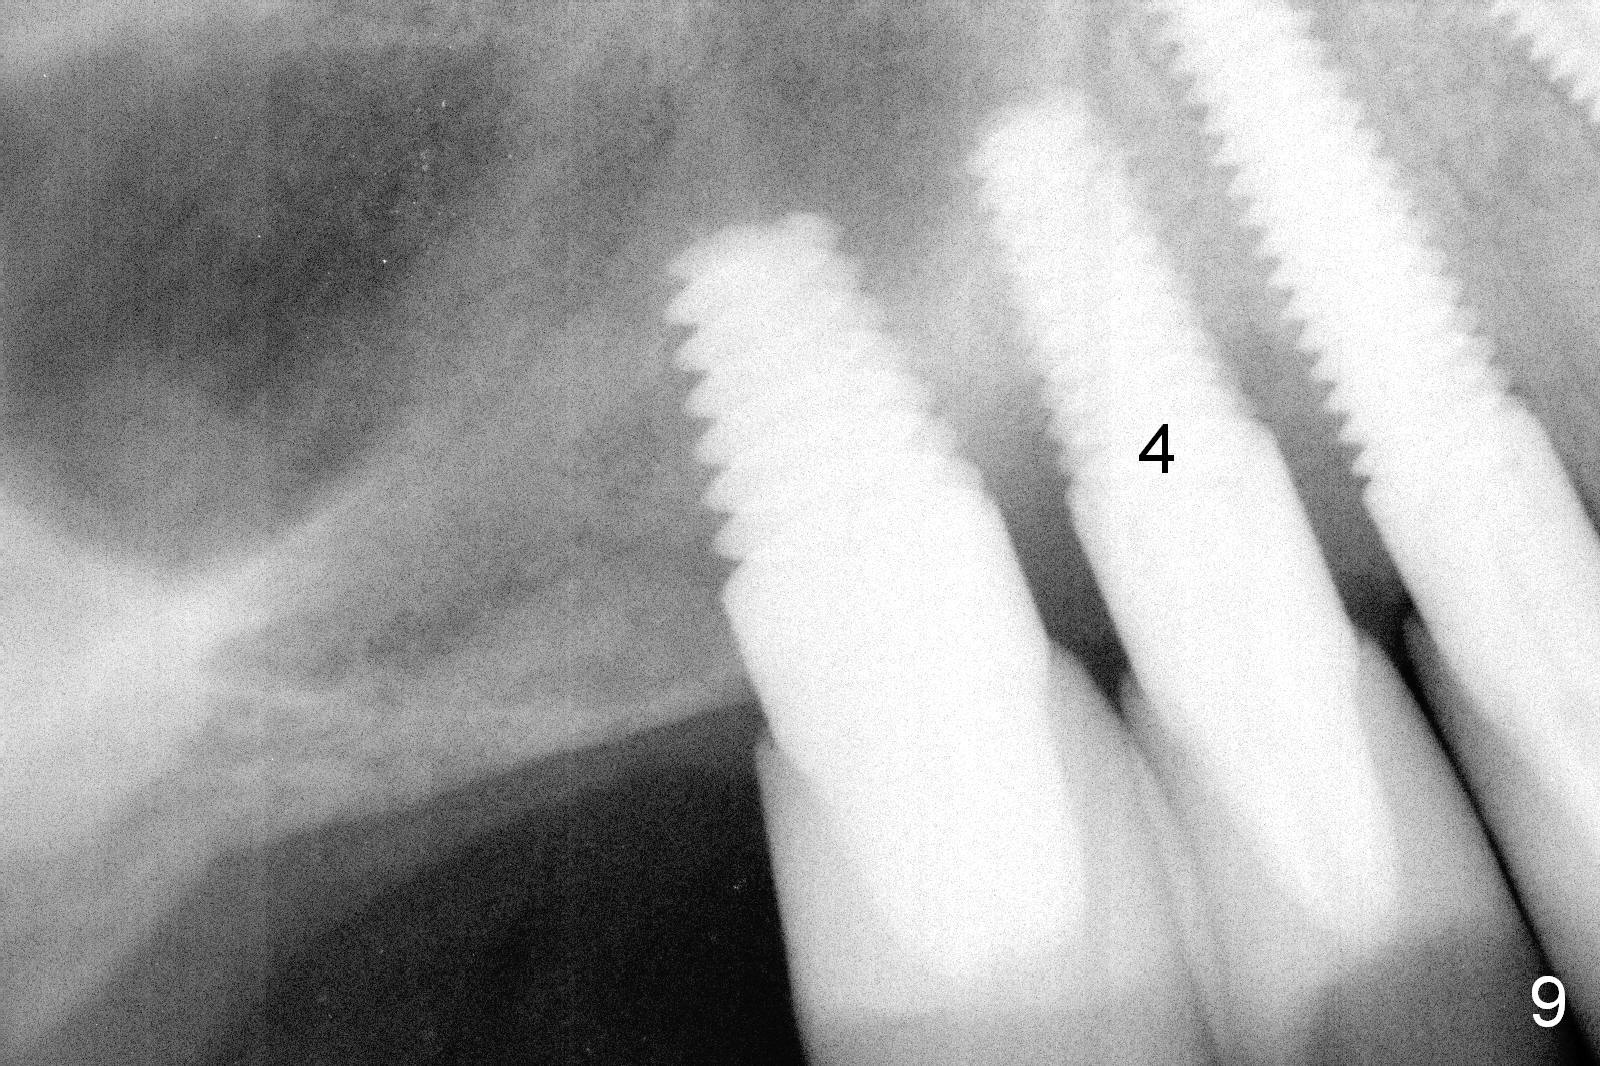

After reconfirmation of the deepest pocket between the implants at #3 and 4, a palatal sulcus incision is made with reflection of the flap. After granulation tissue curettage, a crater is found palatal to the implant at #4 (Fig.1 arrowheads), consistent with preop CT coronal section (Fig.3 *). Another complicating factor is excess temporary cement used for splinted provisional between #3 and 5 (Fig.2 *) between 0.5 and 4 months post #4 implant placement.

The patient returns for follow up 3 months postop. There is no gingival bleeding around the site of #4 palatally (Fig.7) or buccally (Fig.8). There is no further bone resorption (Fig.9).